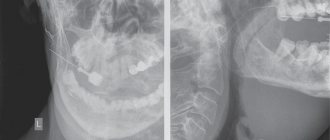

• X-ray to identify foreign formations in the salivary glands. If necessary, the procedure is carried out with the introduction of a contrast agent into the vein;

• X-ray of the gland and floor of the oral cavity, sialography.

• X-ray of the salivary gland;

• Sialography (this is a procedure during which X-ray contrast agents are injected into the salivary duct to help see the presence of salivary stones in the ducts and its location. After this, an X-ray is taken.)